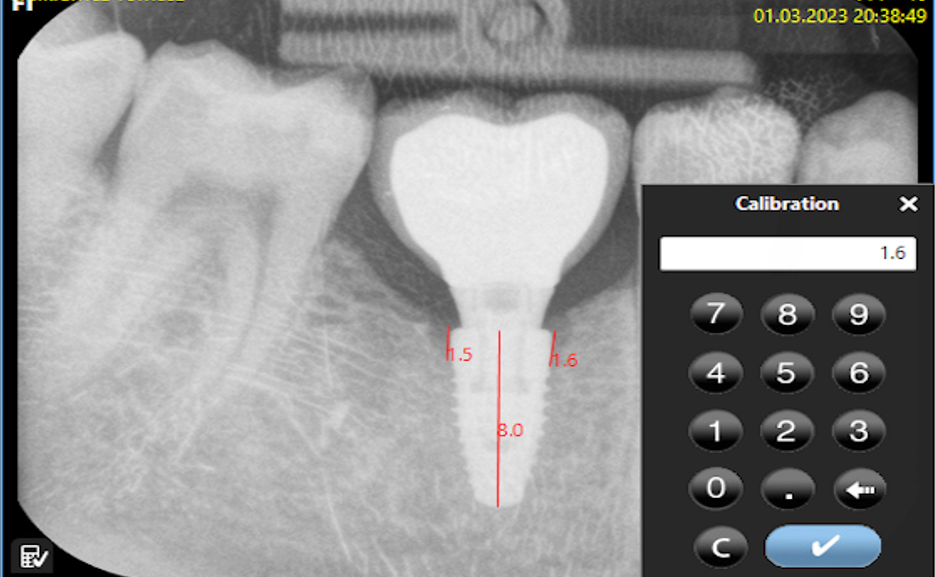

Radiological evaluation of the bone tissue level around implants

Bone loss was assessed using software designed for digital RVG analysis. Each evaluated image was calibrated against the implant length on the RVG and from medical records. The calculated value represented the arithmetic mean of the measurements taken on both sides of the implant, which were visible on the two-dimensional (2D) image. The calculations were made starting from the platform of the implant along its long axis (Figure 3 and Figure 4).

Bone loss was calculated as an average using the following formula (Equation 1):

where:

z – bone atrophy [mm];

zL – bone atrophy on the left side [mm]; and

zR – bone atrophy on the right side [mm].